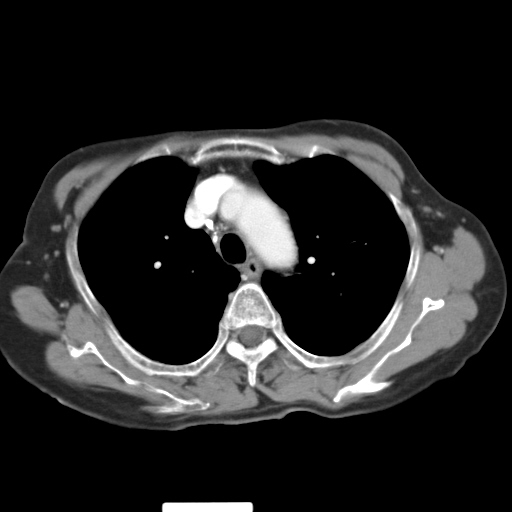

以下是引用hhcckk在2007-3-2 14:51:00的发言:[br]考虑结核球可能性大,依据[br]1病灶在下叶背段,结核的好发部位[br]2病灶内有大量的钙化,纵隔内有大量的淋巴结钙化[br]3重要的是半年前与现在相比无变化,假如是肿瘤的话不会这么‘善良’[br]4病灶周围卫星灶不明显,病灶有毛刺,胸膜凹陷,肿瘤不能完全排除,有条件的话最好做个活检

以下是引用liuyue在2007-3-2 17:15:00的发言:[br]1位置:右上叶后段[br]2性质:大分叶、粗长毛刺、条状斑片状钙化、纵隔多发淋巴结钙化,无强化,故考虑:肺结核灶(陈旧)